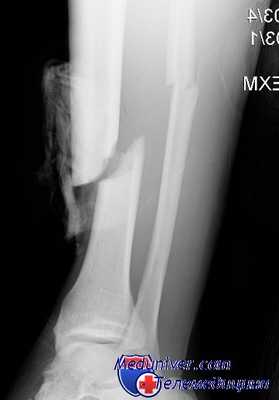

Проявления острого остеомиелита зависят от пути проникновения инфекции, общего состояния организма, обширности травматического поражения кости и окружающих мягких тканей. На рентгенограммах изменения видны спустя 2-3 недели с начала заболевания.

Посттравматический остеомиелит поражает все отделы кости. При линейных переломах зона воспаления обычно ограничена местом перелома, при оскольчатых переломах гнойный процесс склонен к распространению. Сопровождается гектической лихорадкой, выраженной интоксикацией (слабость, разбитость, головная боль и т. д.), анемией, лейкоцитозом, повышением СОЭ. Ткани в области перелома отечны, гиперемированы, резко болезненны. Из раны выделяется большое количество гноя.